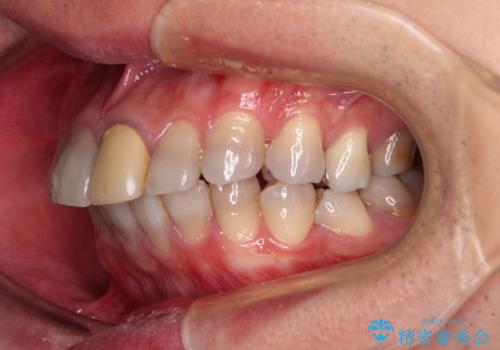

- 飛び出した前歯を気にして来院された患者様です。

口元を引っ込めるために上下左右の第一小臼歯4本を抜歯することとしました。

特徴的な歯の色が気になっているとのことで、今後セラミッククラウンによる審美歯科治療を検討されているとのことで、矯正治療の後戻りが落ち着いたタイミングで治療を進めていく予定です。